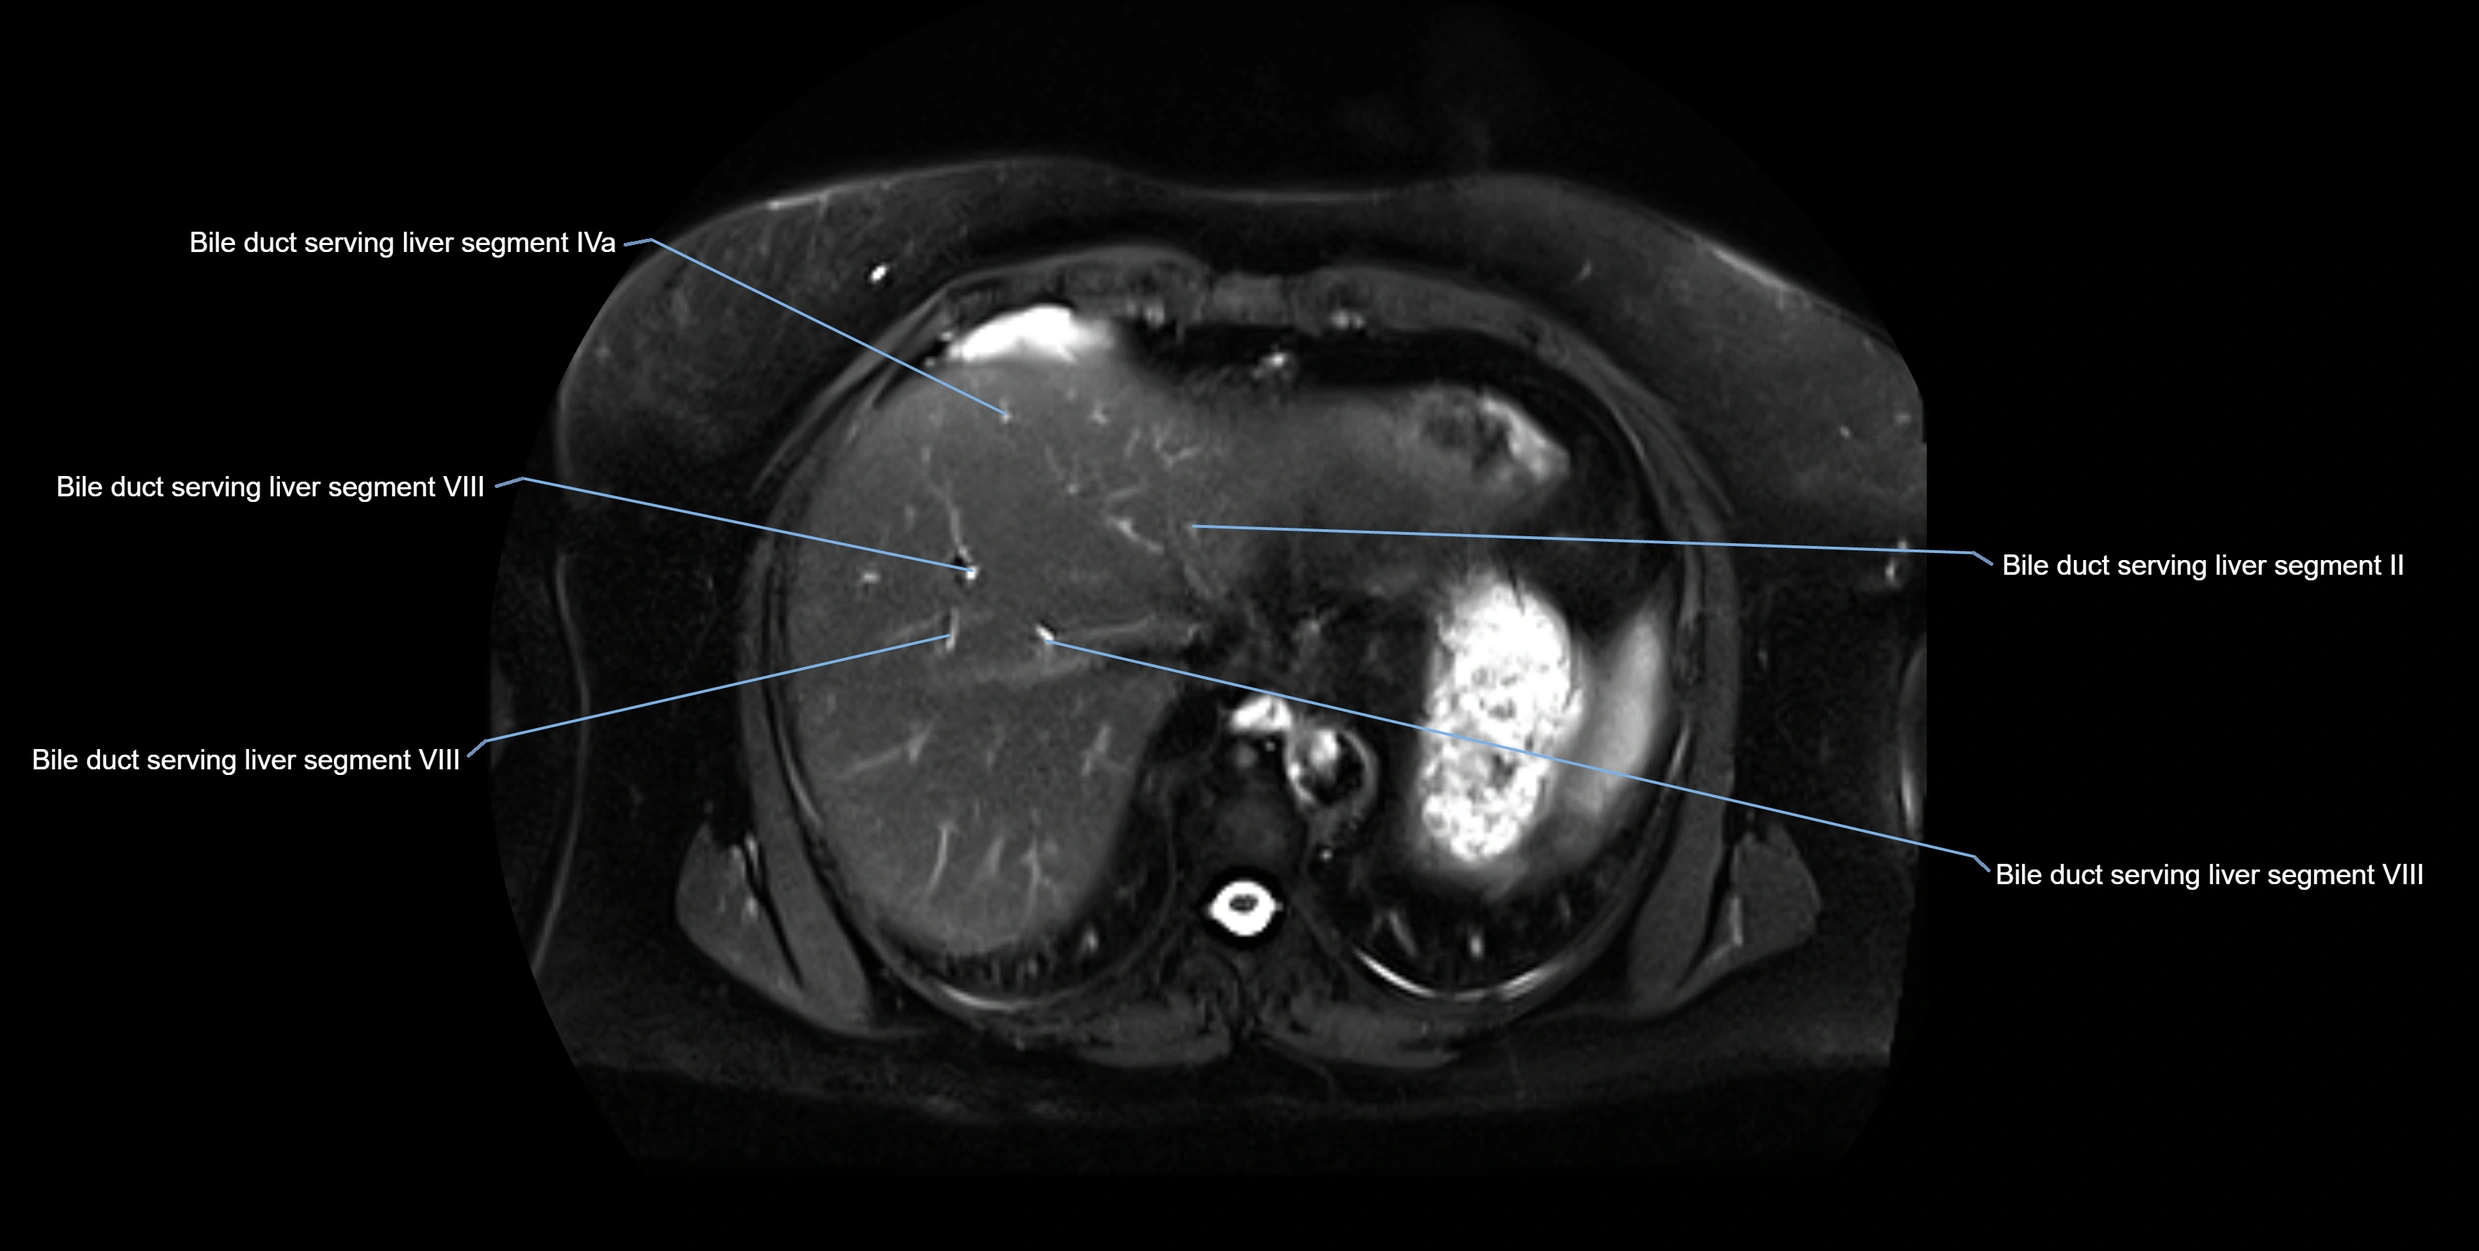

MRI image

image